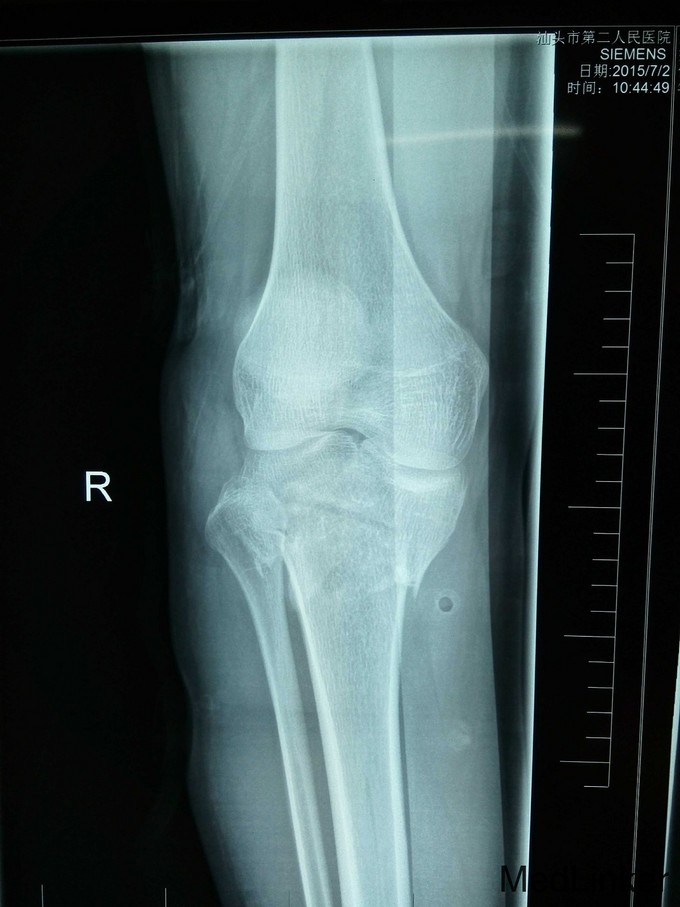

患者,男性,26岁,车祸伤2小时于2015-7-2入院。

右膝高度肿胀,压痛,胫骨结节外侧皮肤擦伤,胫骨外髁有骨檫感,关节活动功能障碍,右踇趾背伸功能减退,足趾感觉无障碍,足背动脉搏动稍弱,右下肢纵轴叩击痛(+)。右膝关节X线及CT检查示:右胫骨平台粉碎性骨折,内外髁骨折并累及关节面,右膝关节MRI检查示外侧半月板损伤,交叉韧带及内侧半月板无明显损伤。

右胫骨平台粉碎性骨折(内外髁骨折) 入院后予跟骨骨牵引,一周后硬外麻下行胫骨平台骨折切开复位内固定术,术后伤口拆线痊愈出院。